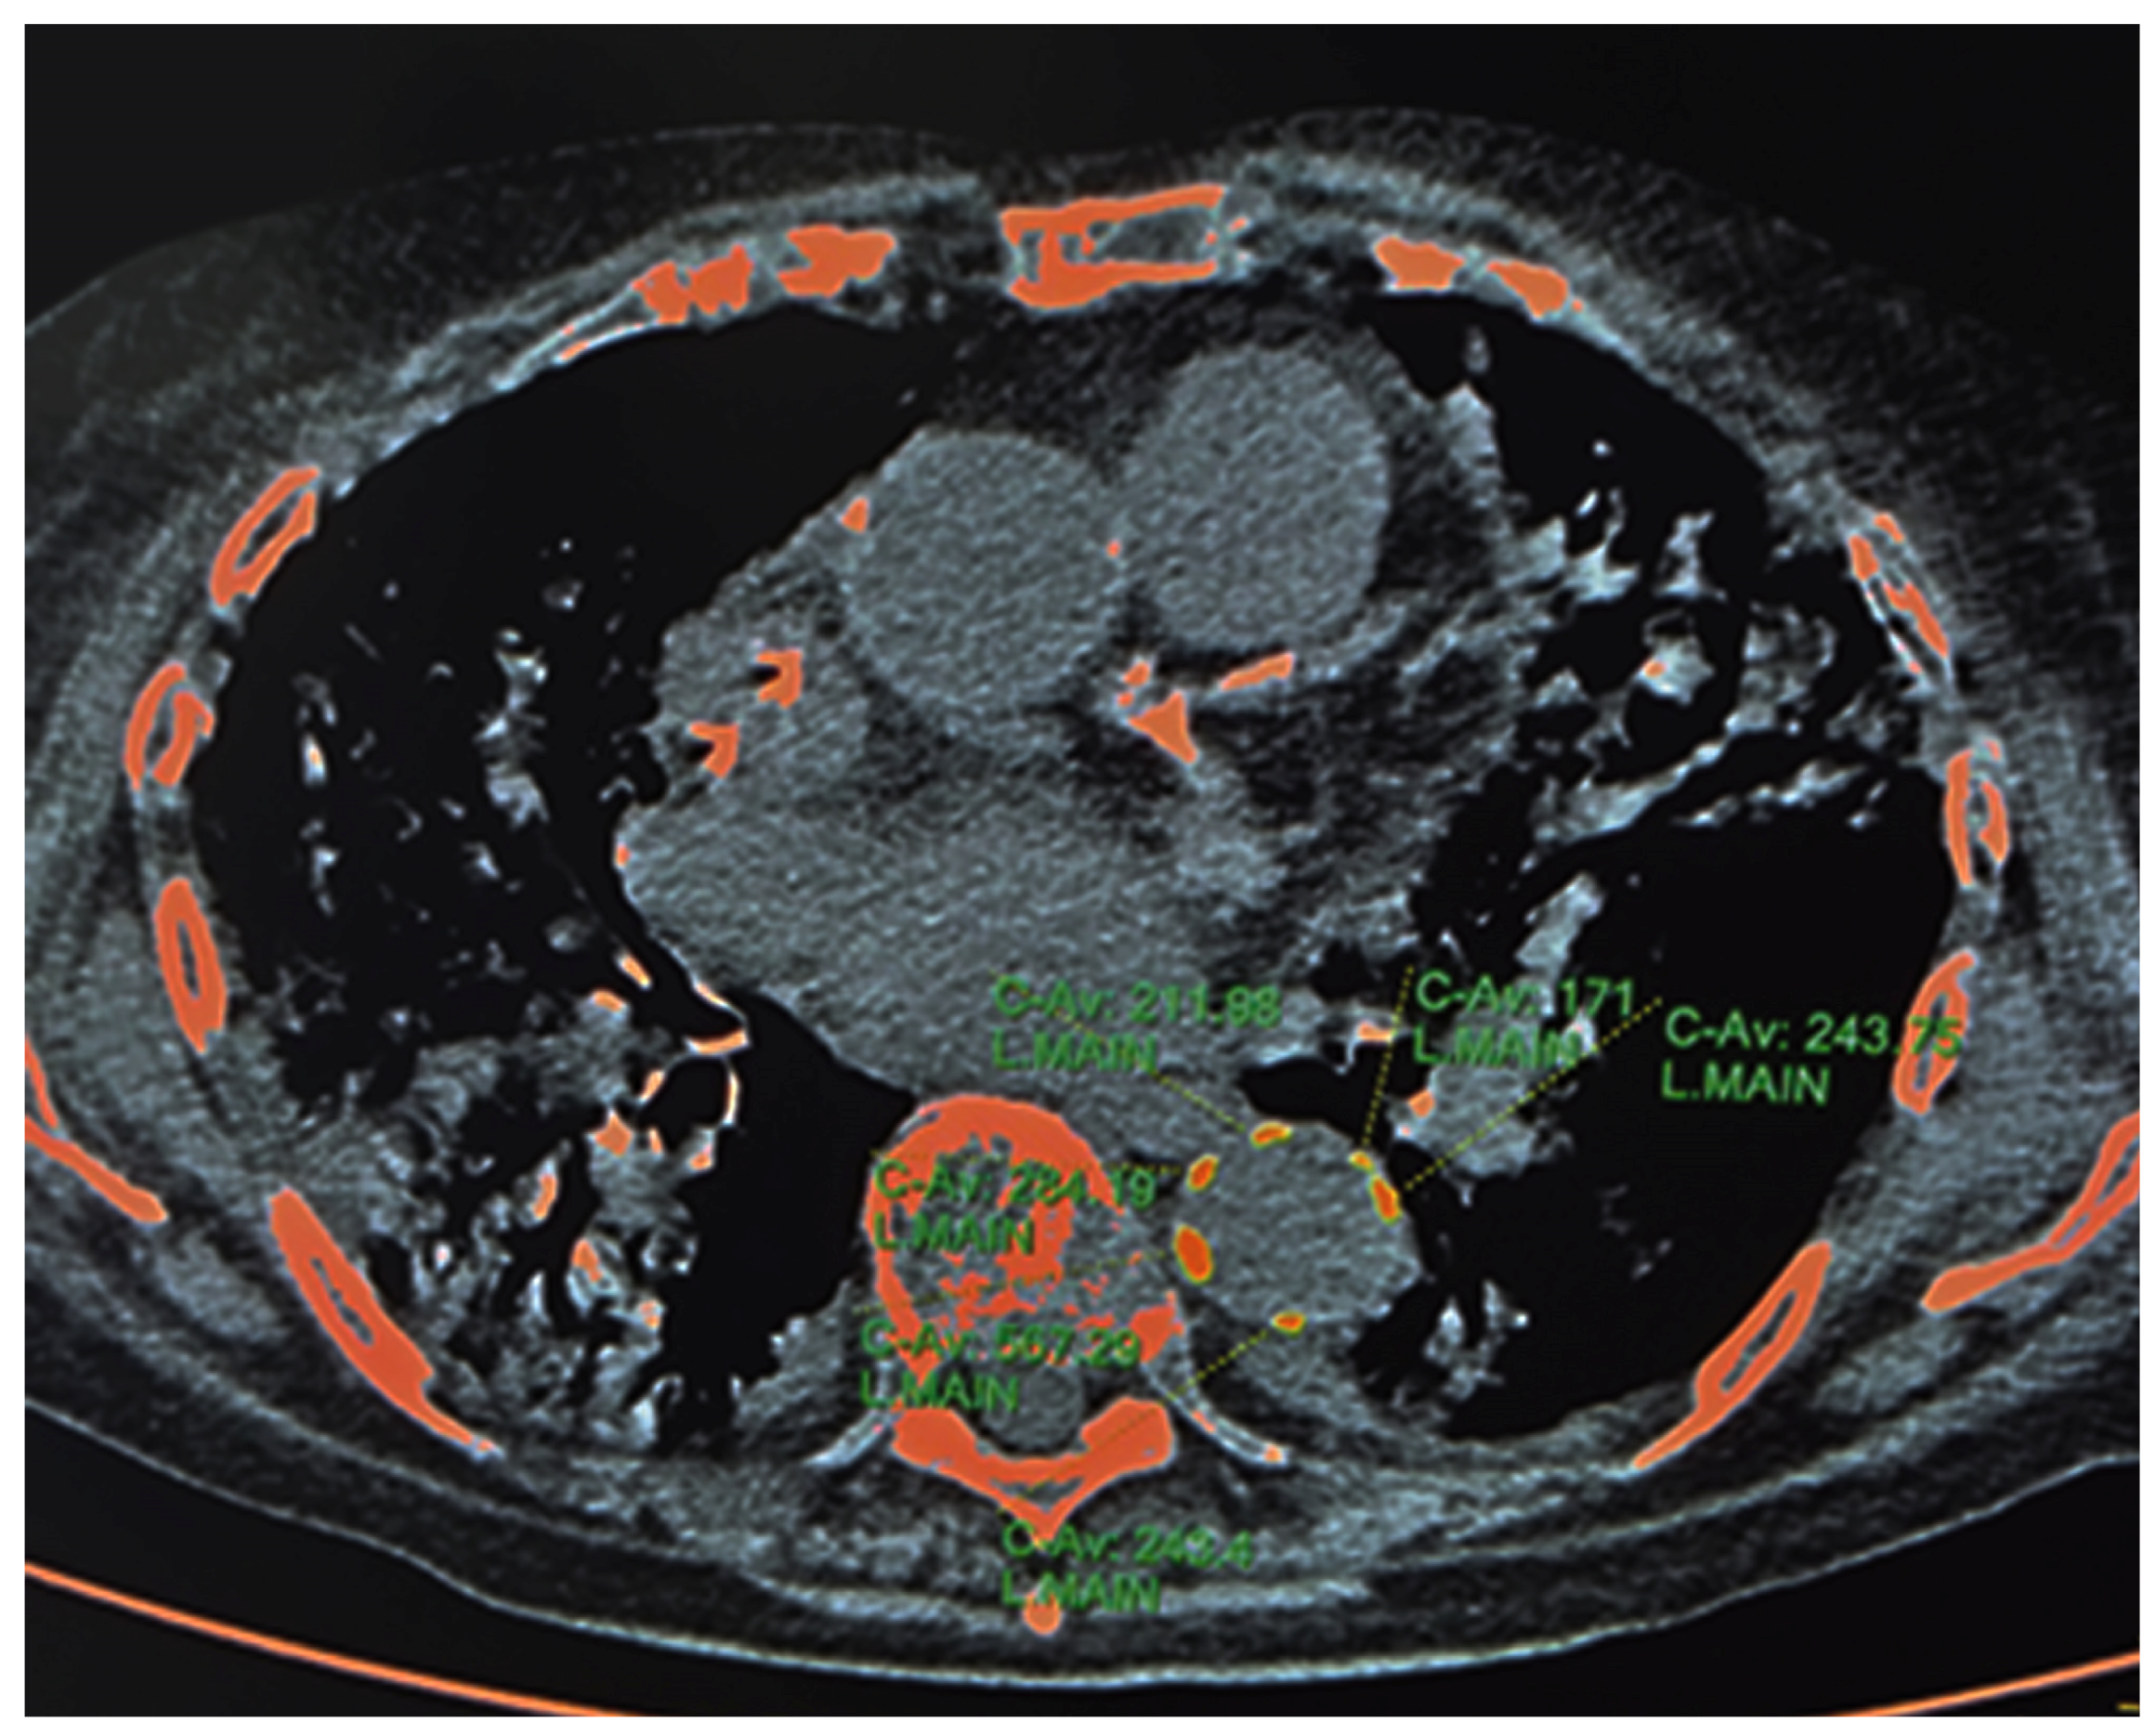

2.3.1. HRCT—Calcium Content of Descending Thoracic Aorta